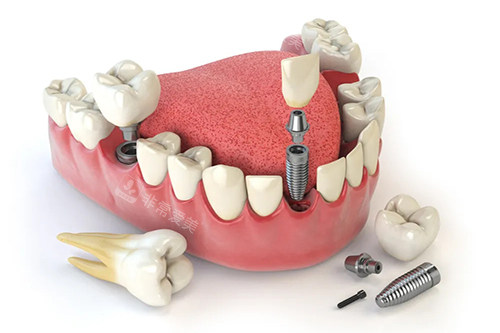

牙齿种植卡通示意图

三、植体稳固耐用有维持

该医院所选用的植体都是经过严格筛选的优质产品,具有良好的生物相容性和稳定性。

植入后,植体能够与牙槽骨紧密结合,就像大树在土壤中扎根一样稳固。

在经过一段时间的愈合后,植体可以承受正常的咀嚼压力,为患者提供持久的使用结果。

此外,医院的医生拥有丰富的种植经验,在植体植入过程中操作比较准,进一步维持了植体的稳固性。